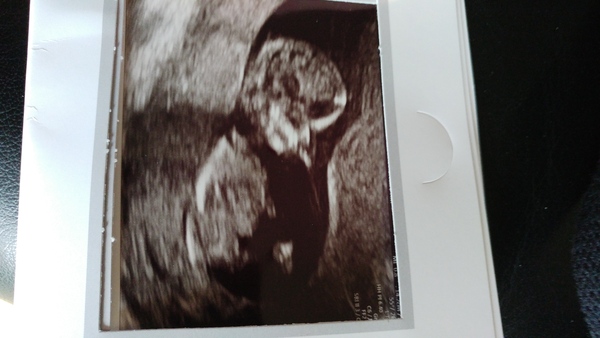

So scan went well very wriggly baby had to move my hips to get it to move for the measurements nt was low risk just need to wait for blood to be processed and with my age to get full risk hopefully in the next week. Moved forward by 5 days so 12+6 today and edd 14th June!

June 2019 Thread 4 - sliding towards 2nd trimester